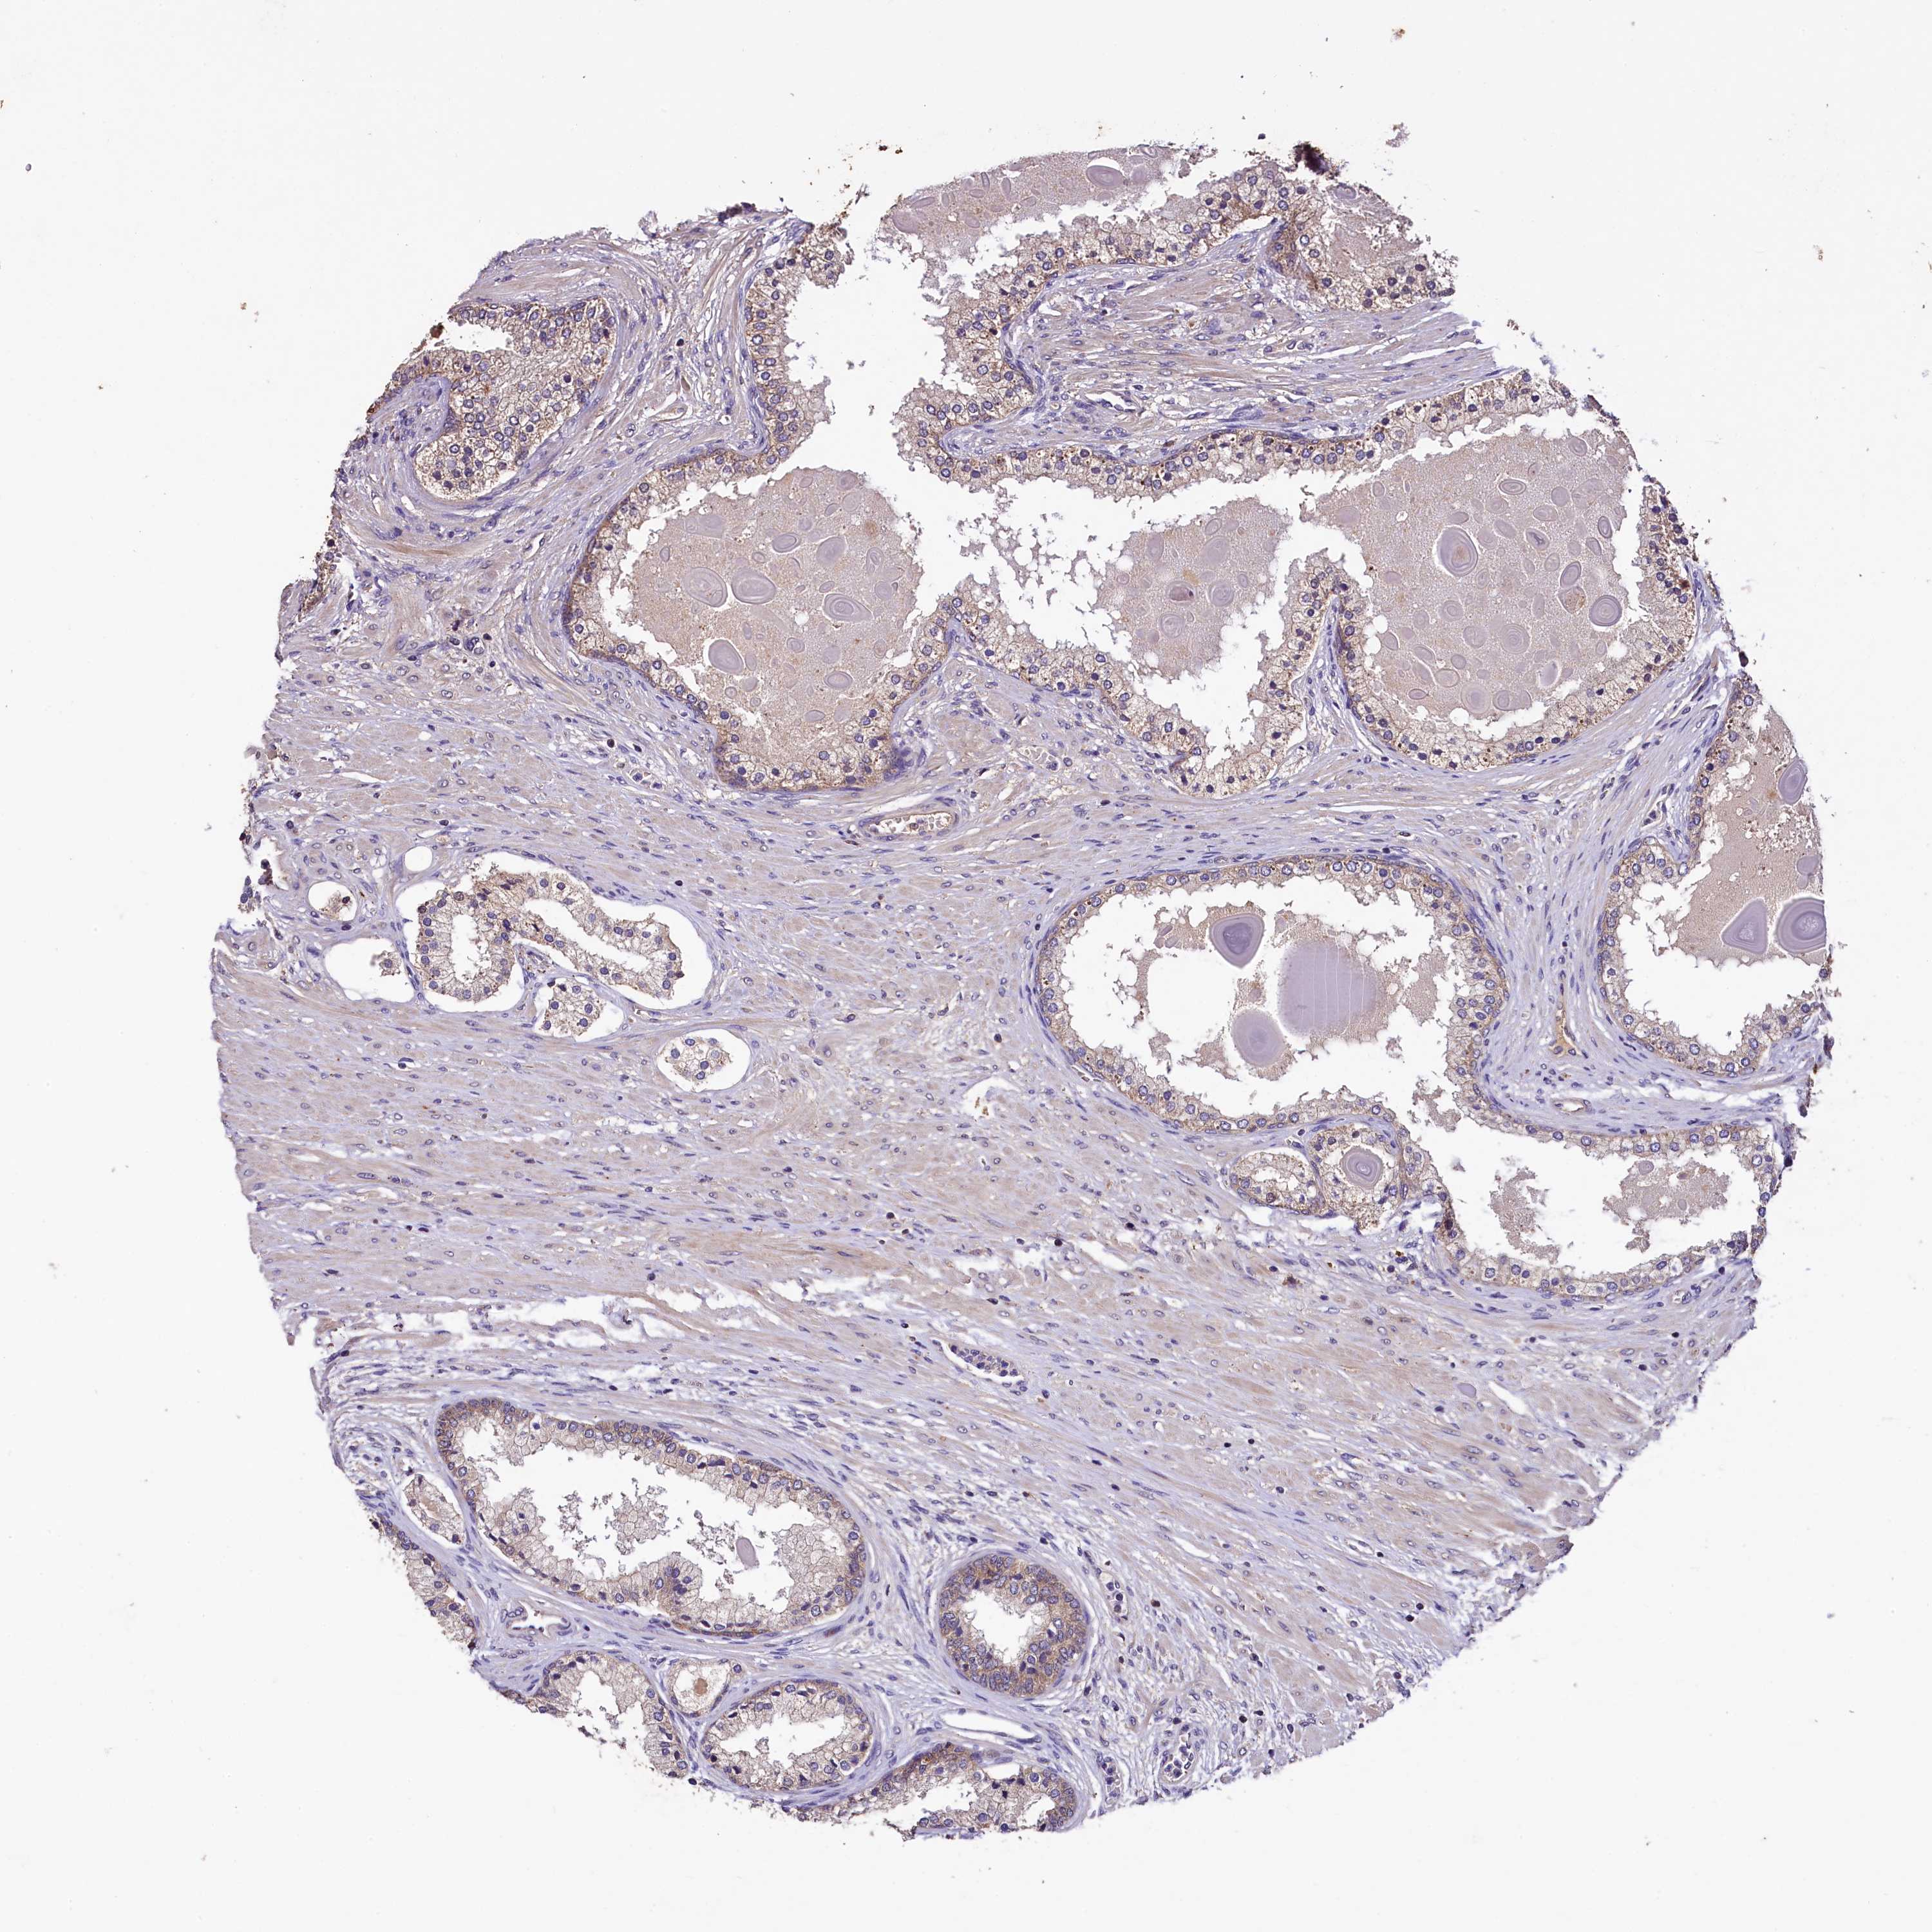

PROSTATE CANCER - Protein expressioni

A mouse-over function shows sample information and annotation data. Click on an image to view it in a full screen mode. Samples can be filtered based on level of antibody staining by selecting one or several of the following categories: high, medium, low and not detected. The assay and annotation is described here.

Antibody stainingi

Antibody staining in the annotated cell types in the current human tissue is reported as not detected, low, medium, or high, based on conventional immunohistochemistry profiling in selected tissues. This score is based on the combination of the staining intensity and fraction of stained cells.

Each image is clickable and will lead to virtual microscopy that enables deeper exploration of all samples and also displays staining intensity scores, fraction scores and subcellular localization as well as patient and tissue information for each sample.

Antibody HPA040586

Staining

High

Medium

Low

Not detected

Intensity

Strong

Moderate

Weak

Negative

Quantity

>75%

75%-25%

<25%

None

Location

Nuclear

Cytoplasmic/membranous

Cytoplasmic/membranous,nuclear

Adenocarcinoma, NOS

Adenocarcinoma, High grade

Adenocarcinoma, Low grade